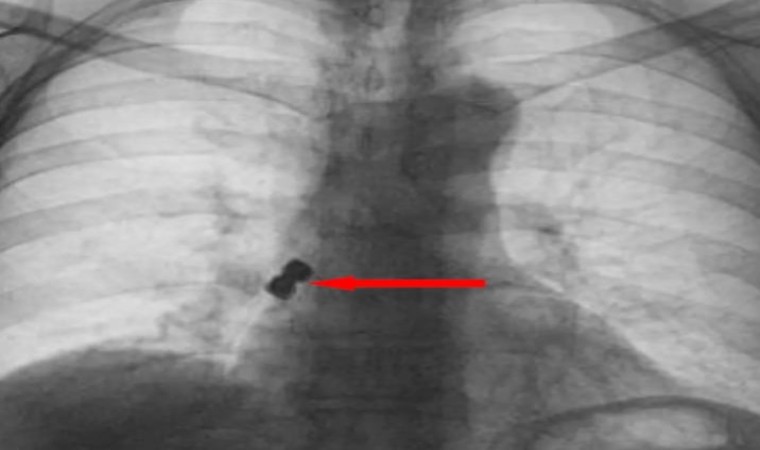

Olay Emirdağ ilçesinde meydana geldi. İddiaya göre, Belçika’nın Brüksel kentinde yaşayan 56 yaşındaki D.K., isimli gurbetçi vatandaş implant diş tedavisi için Emirdağ’daki bir kliniğe gitti. Operasyon esnasında birbirine yapışık halde olan 2 adet implant bir anda hastanın dişinden düştü. İmplantlar ardından hasta yutkununca akciğerlere kaçıp sağ nefes borusunu tıkadı. Nefes almakta zorlanan D.K., ardından Emirdağ Devlet Hastanesi’ne kaldırıldı. Burada yapılan müdahalenin ardından D.K., Afyonkarahisar kent merkezindeki bir hastaneye sevk edildi. Burada D.K.’nın akciğerine kaçan implantlar cerrahi operasyona gerek kalmadan, bronkoskopi yöntemi adı verilen tıbbi müdahale ile çıkarıldı. İmplant yüzünden ölüm tehlikesi atlatan D.K., birkaç gün hastanede kaldıktan sonra taburcu edildi.